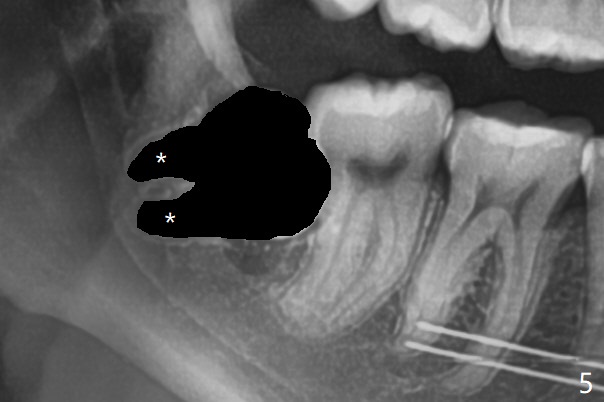

18岁女要求上大学前拔除智齿(图二),十三岁上四已经为了矫正而拔除(图一),所以现在只需要拔除下八,后者接近水平阻生,冠部可能位于下七远中颊侧(图三,四 *),所以附加切口应在七近中(红线)。智齿拔除后根部有两个牙槽窝(图五,六 *)。在右侧,塞入两个胶原塞(图七:1,2,collagen plug),其中一个末端剪开塞入根部牙槽窝。而左侧,使用一个胶原塞,但事先剪成两半(图八:1,3),第一部分也剪成燕尾,插入根部牙槽窝(1),然后在七远中放置骨水泥(1 cc Bond Apatite,2 红色),在后者上面放入胶原塞另外一半(3)。最后两侧都使用4-0 PGA 缝线。

使用胶原塞目的是预防干槽症,以前病例显示它促进骨化中心形成。骨水泥是一种医用性石膏(Biphasic Calcium Sulphate 硫酸钙 ),容易被身体吸收,3个月转换成自体骨。她哥哥(19岁)病例显示骨水泥与Osteogen Plug同样五个月会形成骨质。以后年轻人(25岁以下)智齿拔除不必植骨或者放置骨水泥。左下,右下智齿的确位于第二磨牙颊侧,事先附加切口近中,缝合后伤口不易裂开,骨粉丢失。拔除后即刻拍摄根尖片(图九,十),目的建立原有解剖,与愈合后比较,意外发现断裂牙片(F),后来取出。